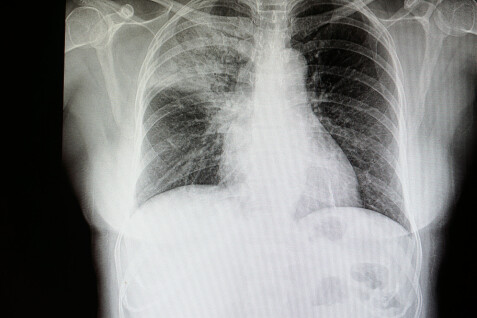

Lungebetennelse pneumoni er en betennelse i lungevevet som skyldes bakterier virus eller sopp. Kjelder Behandling og sjukepleietiltak Lungebetennelse pneumoni Helsefagarbeidaren bind 1 Bente Karin Vatlestad Bilete. Pneumonia is an inflammatory condition of the lung primarily affecting the small air sacs known as alveoli.

Verdens helseorganisasjon WHO anslår at denne sykdommen utløser 16 av dødsfallene til barn under 5 år. Überprüfen Sie die Übersetzungen von lungebetennelse ins Deutsch. Lungevevet vil si lungeblærene alveolene der den livsviktige transporten av oksygen fra luft til blod foregår.

Pneumonia is the accumulation of fluid in the lungs. Schauen Sie sich Beispiele für lungebetennelse-Übersetzungen in Sätzen an. The following 34 files are in this category out of 34 total.

Når lungevevet blir betent kan det bli tyngre å puste.